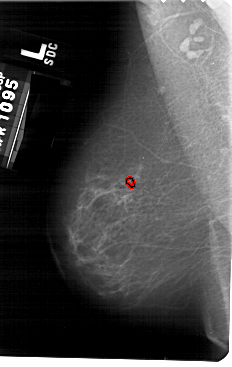

A_1479_1.LEFT_CC

LEFT_CC LINES 5491 PIXELS_PER_LINE 3301 BITS_PER_PIXEL 12 RESOLUTION 43.5 OVERLAY

FILE: A_1479_1.LEFT_MLO.OVERLAY

TOTAL_ABNORMALITIES 1

ABNORMALITY 1

LESION_TYPE CALCIFICATION TYPE PLEOMORPHIC DISTRIBUTION CLUSTERED

ASSESSMENT 4

SUBTLETY 2

PATHOLOGY BENIGN

TOTAL_OUTLINES 1

BOUNDARY